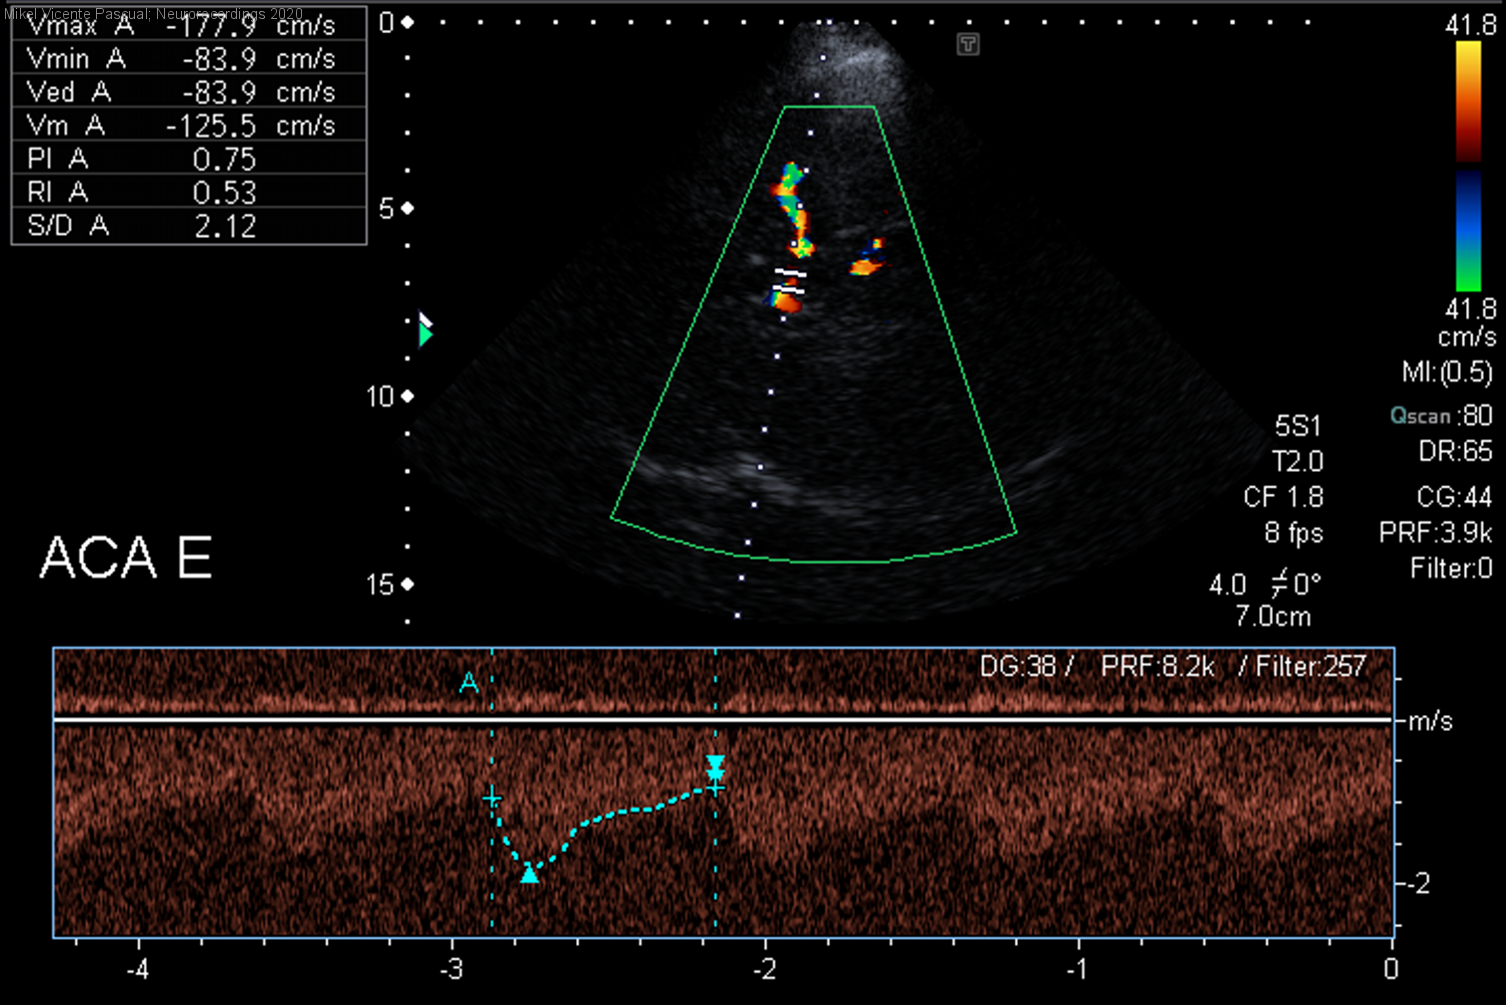

Diagnóstico final: Síndrome de vasoconstricción cerebral reversible

Neurología: Patología cerebrovascular | Cefalea

Resumen del caso

Mujer de 46 años valorada por 3 episodios de cefalea,de inicio súbito, alcanzando un EVA 10/10 a los pocos segundos. El dolor se localizaba en zona occipital y frontal, de características pulsátiles, acompañada de náuseas, vómitos...